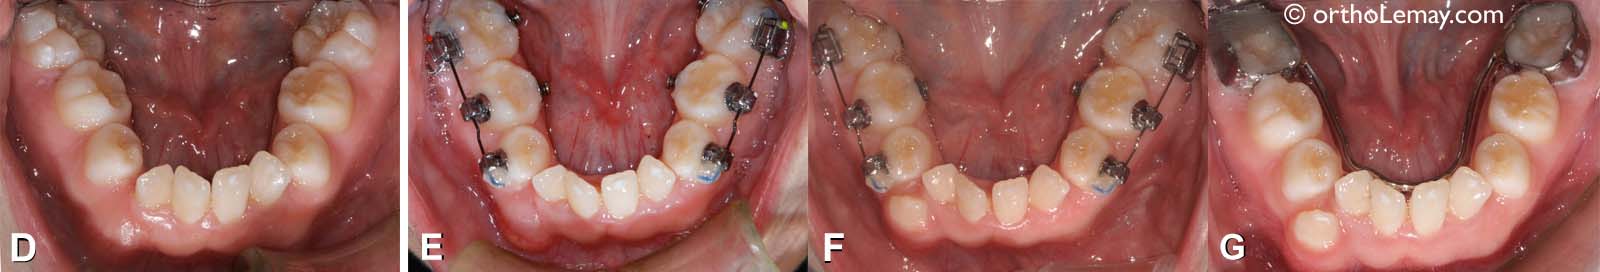

D) Malocclusion

Changements obtenus à l’arcade inférieure

(D) Arcade avant le début du traitement.

(E) Après l’expansion maxillaire et au début de l’expansion mandibulaire.

(F) À la fin de l’expansion mandibulaire.

(G) Après l’expansion mandibulaire, un mainteneur d’espace est utilisé (fil lingual fixe) pour éviter toute constriction de l’arcade et perte de l’expansion obtenue.